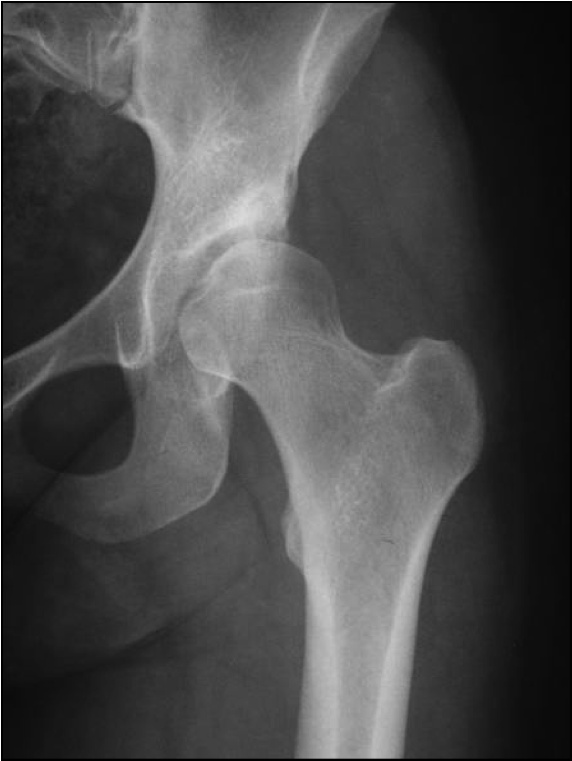

Wir sollen ein Programm schreiben und dann mit GUI ausführen lassen. Das Programm soll ein Röntgenbild (Oberschenkelknochen s. Anhang) einlesen und selbständig erkennen ob es sich um die Aufnahme eines linken oder rechten Oberschenkelknochen handelt.

jetzt die frage wie sollte ich das am besten machen? hat jemand ne idee? Die hochgeladene Datei ist ein linker Knochen. Habe mir evtl. überlegt den Knochen vertikal zu teilen. Danach könnte das Programm gucken auf welcher Bildseite mehr weiße Pixel vorhanden ist und daraus schlussfolgern ob es ein linker oder rechter Knochen ist. Denn wenn z.b. bei einem geteilten bild mehr weiße pixel auf der linken seite sind dann handelt es sich um einen linken knochen und umgekehrt. Muss dazu sagen, dass der Anspruch NICHT der ist, dass das Programm bei jedem Bild funktioniert. Das wäre z.b. eine Idee. Ob es mit Matlab klappt und wie weiß ich nicht deswegen bin ich für jeden Hilfe dankbar!

| Beschreibung: |

| Dateiname: |

Femur.jpg |

| Dateigröße: |

70.61 KB |

| Heruntergeladen: |

730 mal |